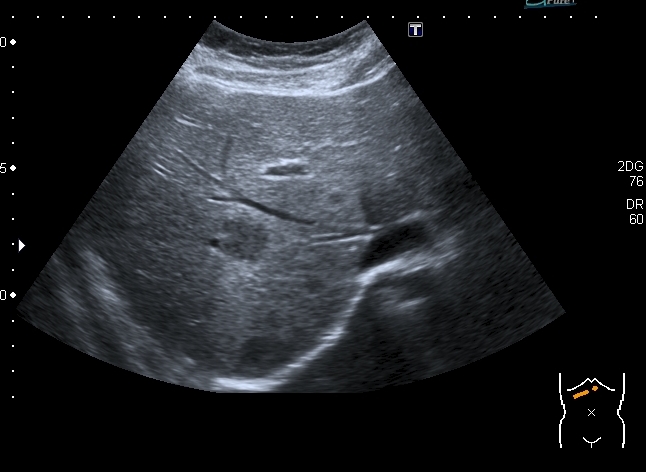

Девочка 13 лет, в течение 2-х недель температура до 38, СОЭ - 40 мм\ч, СРБ - 30.

На УЗИ: Учитывая клинику, лабораторные данные поставил гистиоцитарную инфильтрацию печени и селезёнки при генерализованной инфекции. Несколько раз встречался со схожими случаями, на фоне антибиотикотерапии изменения уходили. Но в данном случае девочка уже получала антибиотики в течение недели, на этом фоне не получено ни клинического , ни лабораторного улучшения, а на УЗИ очаги стали больше. Нужно ли расширять дифференциально -диагностический ряд? Ваши мнения

Имхо, по УЗ-семиотике - множественные небольшие абсцессы.

Мне нравится информация по данной патологии из видаровского "Клинического руководства по ультразвуковой диагностике в педатрии". Там данные изменения носят название очаговых поражений инфекционной этиологии (иерсиниоз, псевдотуберкулёз, токсокароз, хламидиоз и др.). Но инфекционисты, проведя ИФА с очень скудным набором диагностикумов и получив отрицательный результат, так же говорят, что это "не их".

В наше время тактика ведения абсцессов немного изменилась - крупные абсцессы (более 3 см в диаметре) дренируют, мелкие (менее 3 см) лечат антибиотиками.